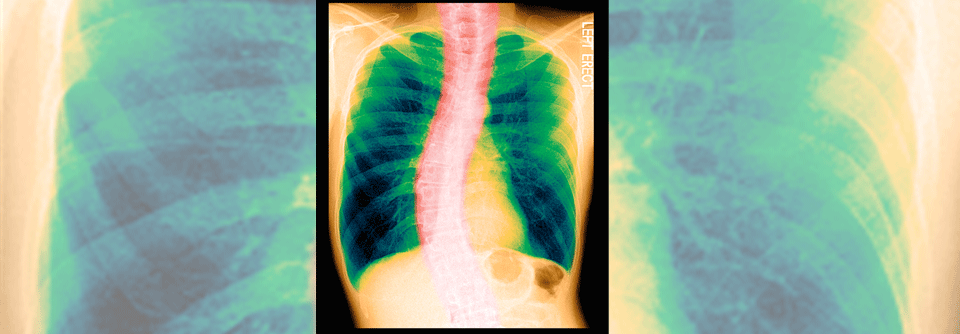

Antibiotika sind bei COPD-Exazerbationen nur selten nötig. Eine deutsche Leitlinie formuliert erstmals, welche Patienten sie nicht erhalten sollen. Antibiotika sind bei COPD-Exazerbationen nur selten nötig. Eine deutsche Leitlinie formuliert erstmals, welche Patienten sie nicht erhalten sollen. © Asier – stock.adobe.com